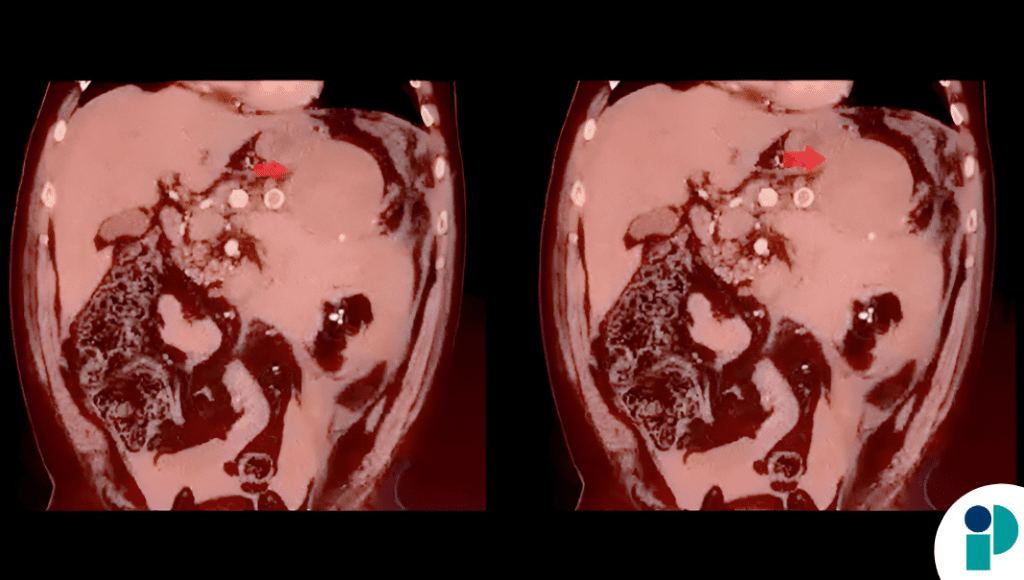

El paciente ingresó al servicio de urgencias con un inicio súbito de dolor abdominal intenso, acompañado de hipotensión severa y colapso circulatorio. Los estudios de imagen realizados de forma urgente evidenciaron la rotura de un gran aneurisma de la arteria esplénica, asociada a hemorragia intraabdominal significativa.

De manera inesperada, evaluaciones posteriores mostraron que la luz del aneurisma se había trombosado espontáneamente tras la rotura. Este fenómeno, extremadamente infrecuente, permitió una estabilización hemodinámica transitoria, lo que brindó un margen de tiempo crucial para la toma de decisiones terapéuticas.